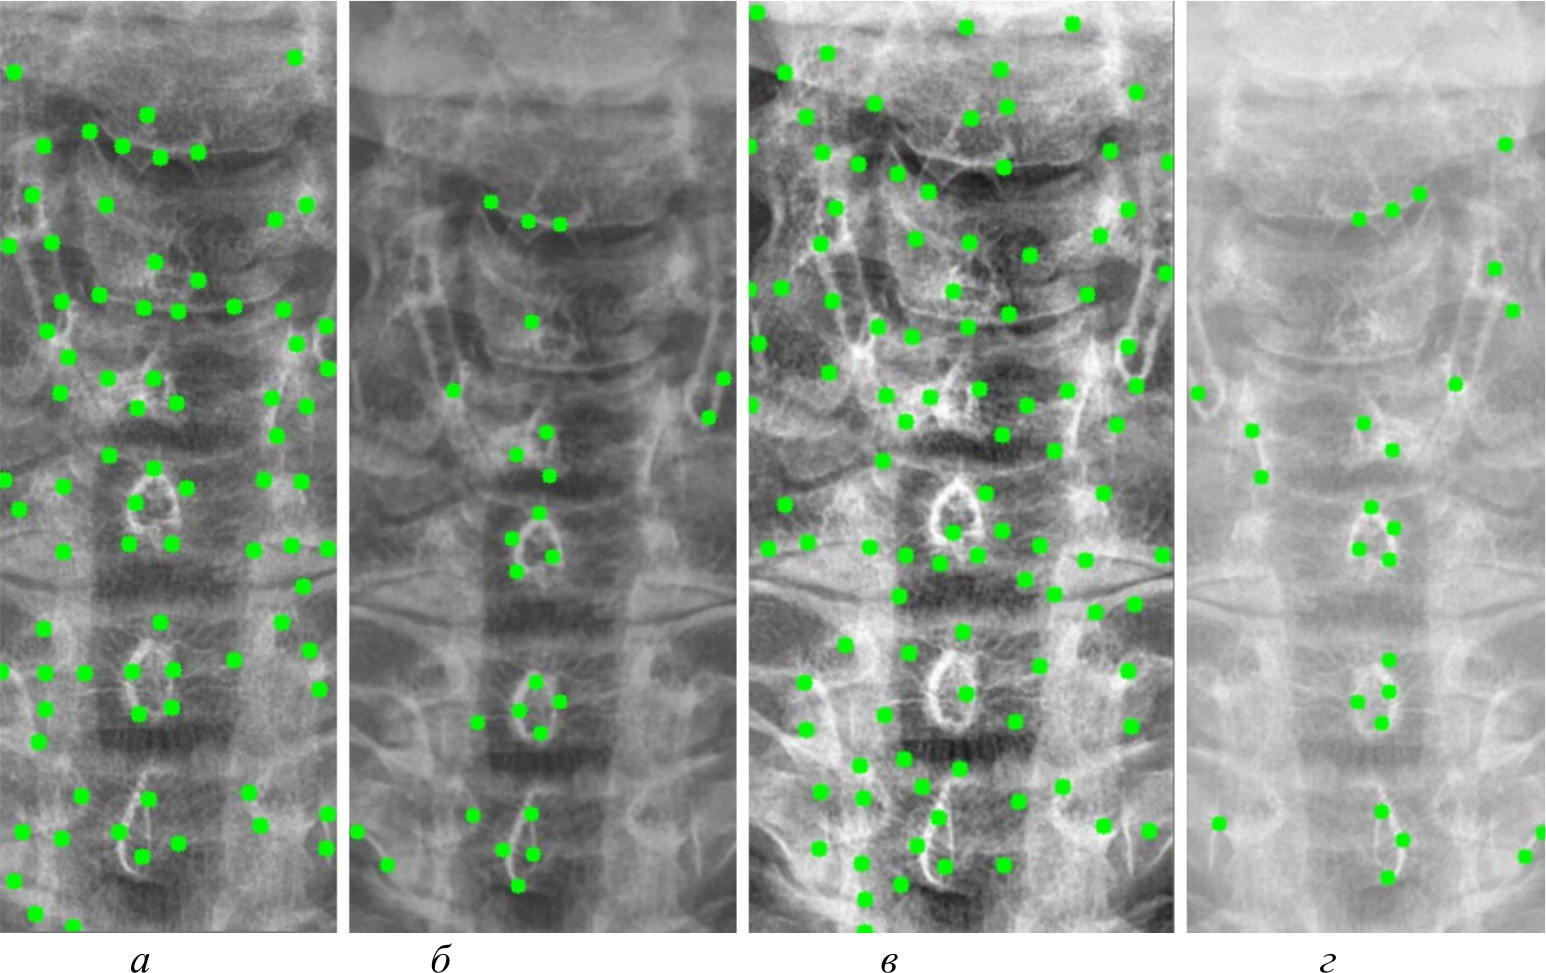

На рис. 4, 5 и 6 представлены результаты работы детектора Харриса, алгоритма Shi-Tomasi и SIFT при различных методах предварительной обработки изображений.

Рис. 4. Результаты работы детектора Harris на изображении, полученном при помощи специализированного программного обеспечения (а); результаты работы детектора Harris при методе адаптивной эквализации гистограммы (б); результаты работы детектора Harris при методе стандартной эквализации гистограммы (в); результаты работы детектора Harris при методе гамма-коррекции (г)